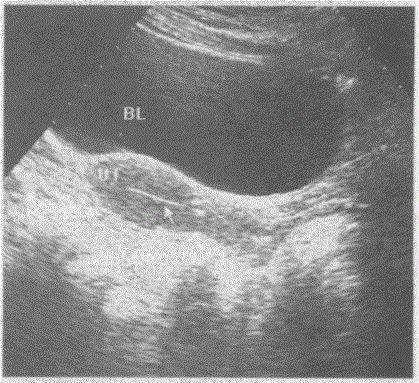

问题 下图是子宫纵切超声图像,请回答箭头所指部位的解剖名称:

选项 A.子宫内膜 B.子宫内节育环 C.子宫内异物 D.宫腔内积气

答案 A